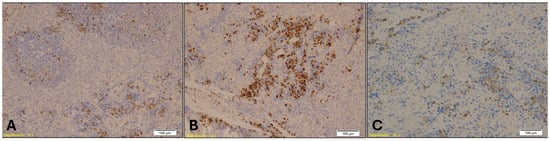

- Myeloperoxidase (MPO) (rabbit monoclonal, 1:100)—Lung and Spleen: MPO is a non-specific marker of neutrophilic infiltration and oxidative stress. It is used to evaluate inflammatory responses and immune activation, which may be altered in hypothermia and further modulated by alcohol or benzodiazepine exposure.